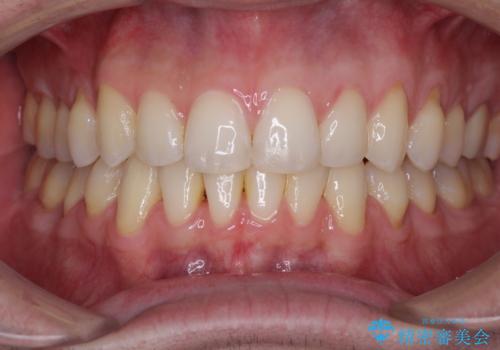

ディープバイトと叢生 インビザラインによる矯正治療

上下ともに叢生が認められたため、親知らずすべてを抜歯し、歯列全体を後方へ移動させることで歯列を整えることとしました。

上顎奥歯の銀歯も気になっていたので、矯正治療の途中でセラミッククラウンへ変更し、その後歯列を仕上げていくこととしました。

ディープバイトもデコボコも改善され、気になっていた銀歯もセラミックとなり、患者様には大変満足していただきました。